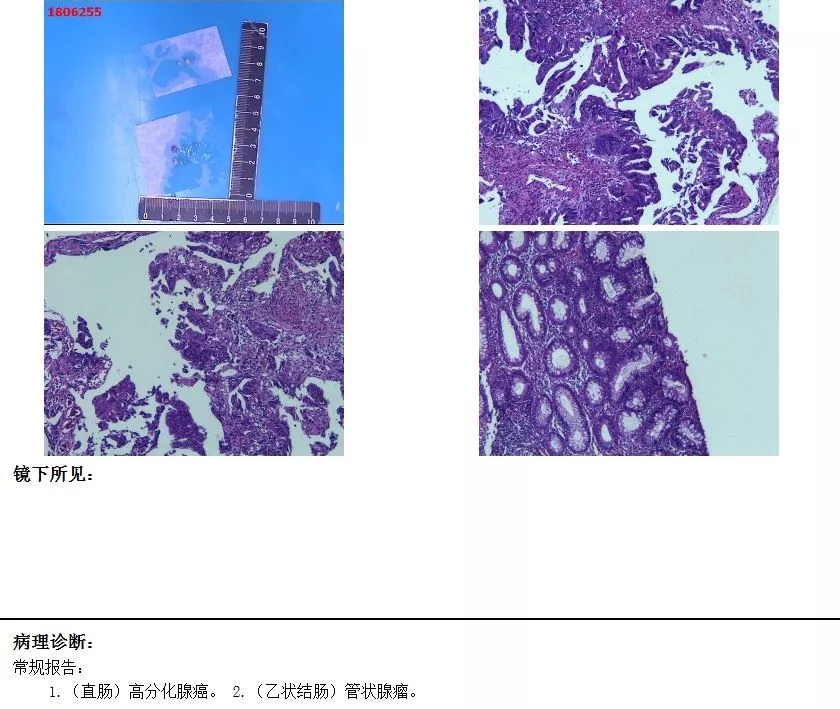

经肛肠科医生直肠指检发现距离肛管齿线3-7cm有个菜花状直肠肿物占据肠腔一半以上,其中一小部分占据肠腔3/4,直肠部分狭窄,肠镜和病理检查确诊为直肠中分化腺癌,建议她尽快行手术治疗。

术前病理结果 中分化腺癌

术后病理结果 未见癌细胞 部分粘膜高级别瘤变

术前病理结果 高分化腺癌

术后病理结果 癌瘤成分消失